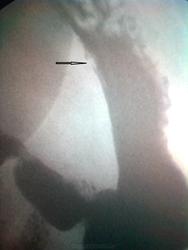

Больная, 73 года, жалобы на боли в эпигастральной области, усиливаются после еды, тошноту, иногда - рвоту, горечь во рту. болеет около двух месяцев. Клинические анализы без особеностей. УЗИ - хр. панкреатит, холецистит. Рентгеноскопия желудка: некоторое утолщение складок слижистой в антральном отделе, деконфигурация в виде продольных складок в верхнем горизонтальном отделе ДПК. эвакуация, перистальтика - бех особенностей. При тугом наполнении в правом косом положении больного по малой кривизне мелкий стойкий дефект наполнения с подрытостью контура. (Снимки сделаны с экрана и прицельного снимка камерой телефона - извините за качество).

Язва с выраженным воспалительным валом, принятым за дефект наполнения на контуре.

Похоже малый рак, очень интересно дальше. Малые - редко кому удается выявить

. По язве- здесь + ткань , а не дефект ткани. Возможно подслизистый?

Дефект стойкий, при глубокой пальпации не исчезает и только в этой проэкции. Ни на рельефе, ни в другой проэкции я его не видел, потому и не снял. Извините. ЭГДФС нам скорее всего поможет!